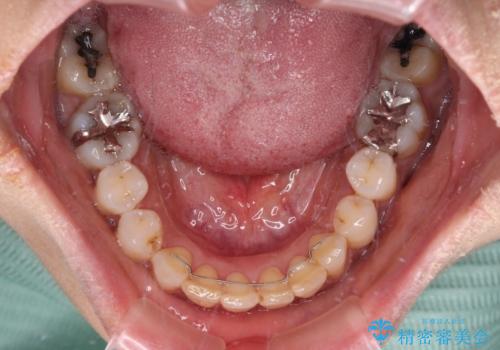

なかなか装着時間が守れず、後戻りを繰り返しながら治療を進めたため、インビザライン治療期間期限ギリギリの5年弱の期間を要しました。

- マウスピース型矯正装置の長時間装着(1日20時間以上)が必須です

- 治療計画通りに進めるためには、患者様の意志が重要になります

- 矯正治療後の保定が不十分だと後戻り(元の位置に戻ろうとする動き)をします